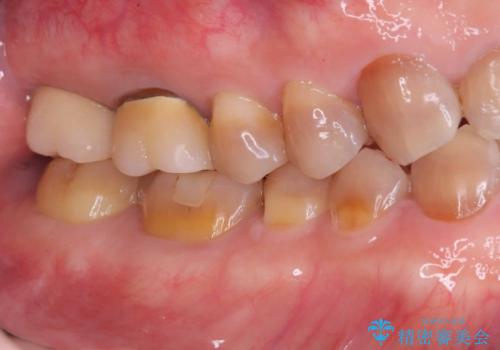

抜歯と歯根嚢胞の除去を行った後、インプラントで治療しました。治療後は「自分の歯のように咬める」と大変ご満足いただけました。